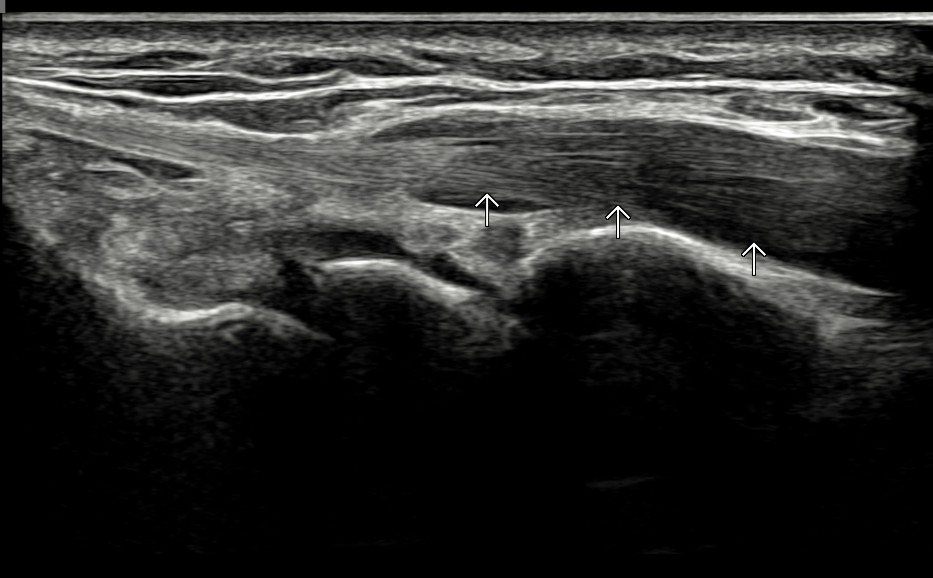

치료 후기에 사용된 전/후 검사 사진은 동일 인물의 결과이며 각 지점 동일 조건에서 촬영되었습니다.

개인에 따라 치료 결과에 차이가 있을 수 있으며, 부작용이 발생할 수 있습니다. 내원 후 충분한 상담을 받으시고 치료를 진행하시면 됩니다.

- 치료기간 : 25 .5 30 . ~ 25 . 6 .27

- 치료횟수 : 5 회(dna 1cycle)